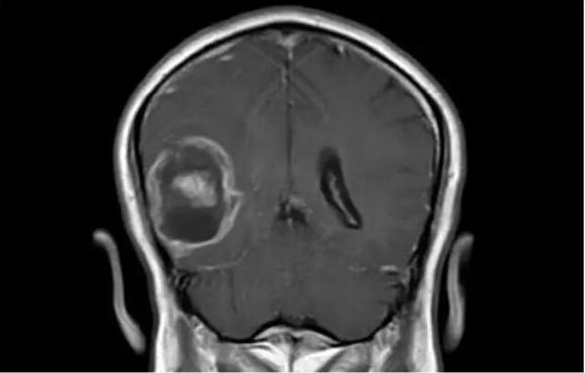

IBM 沃森分析了脑肿瘤的基因组数据。图片来源:fiercebiotech

这项探索性的研究是在一位胶质母细胞瘤的患者身上进行的。胶质母细胞瘤是一种非常凶险的癌症,死亡率很高,确诊后的平均存活时间不到 15 个月。对于这样的癌症患者来说,时间是极其宝贵的,越早找到有针对性的治疗方案,就越有可能延长患者的生命。